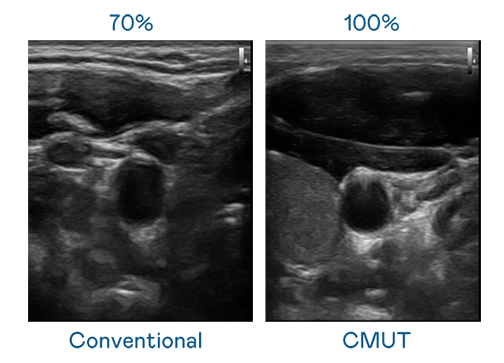

CMUT 技术是一种用电容式微机电元件来产生超音波讯号的技术。与传统 PZT 压电式技术相比,CMUT 频宽增加 30%,更宽频的超音波讯号让影像解析度大幅提升,是实现高影像品质医疗超音波扫描、促进精准医疗发展的关键技术。

大频宽带来超清晰影像

超音波影像的解析度高低,首先取决于探头能发出的讯号频宽。z6人生就是博 CMUT 可提供高清晰的超音波讯号,提供高频宽、高灵敏度、影像纹理细节更高的超音波影像,协助医护人员缩短影像判读时间及利用精准的医疗影像进行诊断。